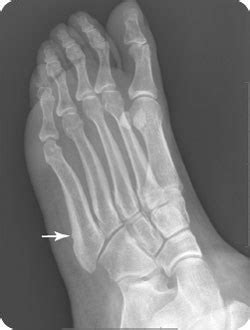

Very rarely is it necessary to operate on these fractures acutely. Avulsion fractures of the tuberosity are the most common fractures involving the proximal fifth metatarsal. 5th metatarsal fractures can vary in location, severity and type including avulsion fracture, stress fracture, jones' fracture, displaced fracture signs and symptoms of a 5th metatarsal fracture. Traditionally this avulsion fracture has been ascribed to the insertion of peroneus brevis and is caused by forcible inversion of the foot in plantar flexion radiographic features. I rolled my ankle on 5 october and broke 4th and 5th. Os peroneum is an accessory bone (ossicle) located at the lateral side of the tarsal cuboid, proximal to the base of 5th metatarsal, commonly mistaken for a fracture. When there is significant displacement a in rare situations it may be necessary to undertake reconstructive surgery which would repair not only the fracture (often with bone grafting). Fifth metatarsal fracture, proximal fifth metatarsal fracture, jones fracture, fifth metatarsal base fracture. I am 6 weeks post surgery on my 5th displaced metatarsal fracture. 5th metatarsal fractures have been quite common among elite soccer players in the english premier league over the past five years. Jones fracture is a difficult fracture to heal due to limited blood supply to that area and often surgery. This one is tricky.due to the specific vascularity in that region it is of uttmost importance to properly select surgical candidates. Fractures of the proximal fifth metatarsal pose an important diagnostic challenge.

Acute diaphyseal fractures tend to occur near the metaphysis and the mechanism is usually a crush injury or an inversion force that causes avulsion by the peroneus brevis tendon. Athletes are allowed to bear weight on the foot immediately following surgery in a boot, but limit impact loading of. Fractures of the proximal fifth metatarsal pose an important diagnostic challenge. I am 6 weeks post surgery on my 5th displaced metatarsal fracture. Generally athletes will have surgery to improve odds of healing.

When there is significant displacement a in rare situations it may be necessary to undertake reconstructive surgery which would repair not only the fracture (often with bone grafting). Traditionally this avulsion fracture has been ascribed to the insertion of peroneus brevis and is caused by forcible inversion of the foot in plantar flexion radiographic features. Related online courses on physioplus. 5th metatarsal base fractures are common traumatic fractures among athletic populations that are notorious for nonunion due to tenuous blood supply. Formulary drug information for this topic. If not displaced or comminuted, these fractures uniformly heal well with. Patients with this condition typically experience a sudden onset of sharp, intense outer foot or ankle. An avulsion fracture is a bone fracture which occurs when a fragment of bone tears away from the main mass of bone as a result of physical trauma. Fifth metatarsal fractures are notoriously slow healing fractures, but after ten weeks, especially since you had surgery, under most circumstances you. Acute diaphyseal fractures tend to occur near the metaphysis and the mechanism is usually a crush injury or an inversion force that causes avulsion by the peroneus brevis tendon. A small piece of bone is pulled off the main portion of the bone by a tendon or ligament. An avulsion fracture happens at the most proximal end of the bone. I had a 5th metatarsal fracture 13 weeks ago.

The 5th metatarsal is the outer bone that connects to your little an avulsion fracture occurs when a tendon pulls a piece of bone away from the rest of the bone. Fifth metatarsal fractures are notoriously slow healing fractures, but after ten weeks, especially since you had surgery, under most circumstances you. Most common fracture at base of 5th metatarsal. Based on landmarks along joint between 4th and 5th metatarsals proximally. Avulsion fractures of the fifth metatarsal base:

Jones fracture - Wikipedia from upload.wikimedia.org Sx often mild, patients usually present with sprained ankle complaint. When there is significant displacement a in rare situations it may be necessary to undertake reconstructive surgery which would repair not only the fracture (often with bone grafting). I am 6 weeks post surgery on my 5th displaced metatarsal fracture. Examples include midshaft fractures if the injury involves a displaced bone, multiple breaks or has failed to adequately heal, surgery may be required. Patients with this condition typically experience a sudden onset of sharp, intense outer foot or ankle. Traditionally this avulsion fracture has been ascribed to the insertion of peroneus brevis and is caused by forcible inversion of the foot in plantar flexion radiographic features. An avulsion fracture happens at the most proximal end of the bone. While this injury needs to be distinguished from.